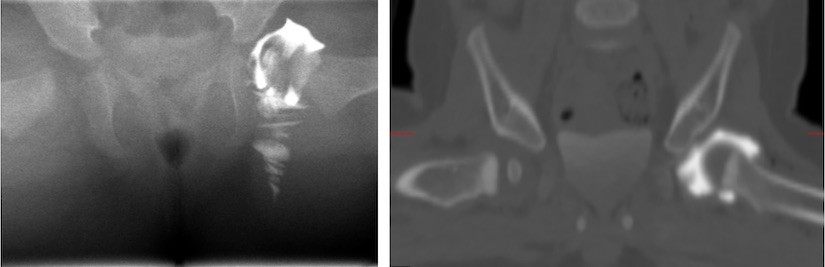

Links: röntgenfoto van een kind van 4 maanden oud met contrastvloeistof (wit) rond de heupkop.

Rechts: CT-scan van een kind van 9 maanden oud met contrastvloeistof (wit) rond de heupkop.

Bij baby’s met een heupluxatie kan op deze manier worden gekeken of er weefsel in de heupkom zit dat de heupkop uit de kom drukt. Als dit het geval is, is in veel gevallen een open repositie nodig om het weefsel weg te halen. Meestal wordt dit dan meteen gedaan zodat het kind niet nogmaals onder narcose hoeft.

Een arthrogram is een röntgenfoto die is gemaakt nadat er contrastvloeistof in het gewricht is gespoten. Met behulp van deze vloeistof kun je op een röntgenfoto de ruimte tussen de heupkop en de heupkom in beeld brengen. Afhankelijk van de onderzoeksvraag kan na het maken van het arthrogram ook nog een CT-scan of MRI-scan worden gemaakt. Dit wordt dan een CT-arthro of MRI-arthro genoemd.